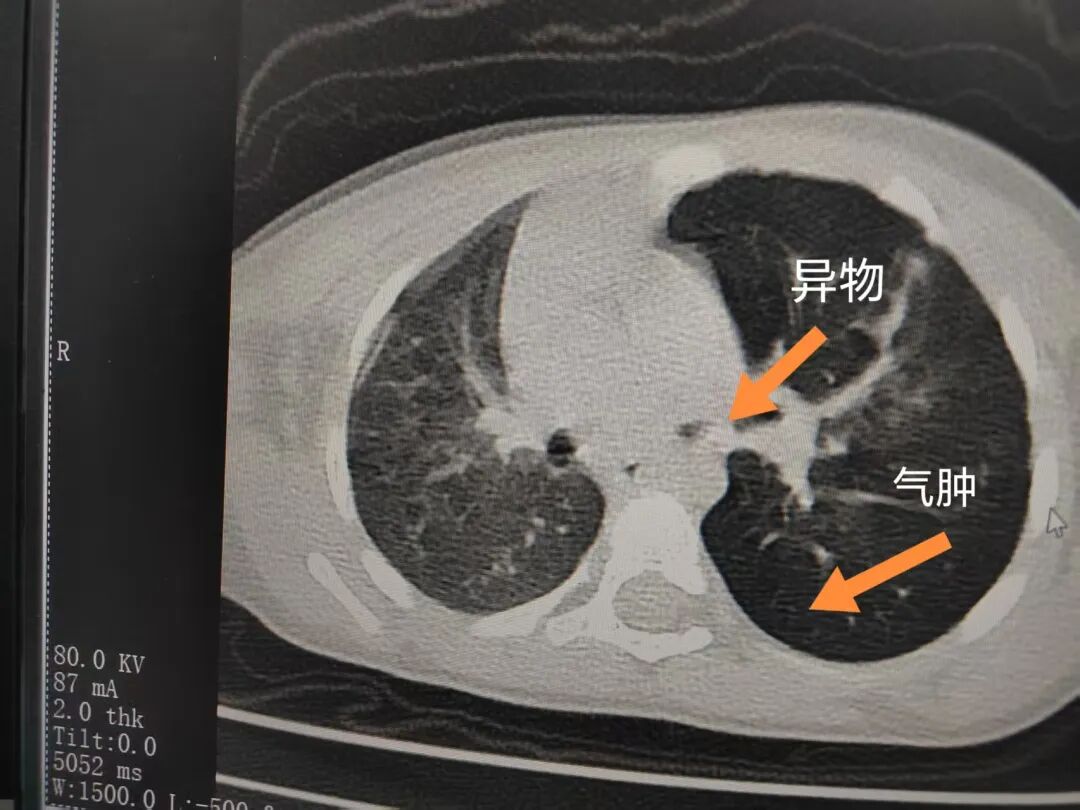

三天后(11月13日),趙寶出現(xiàn)高熱、咳喘加重,家長(zhǎng)著急了,再次帶他來(lái)到醫(yī)院。CT檢查顯示左肺過(guò)度充氣,左肺上下葉支氣管主干見(jiàn)不規(guī)則高密度影,左肺上葉可見(jiàn)大片狀密度增高影,縱隔窗實(shí)變,提示為“左側(cè)支氣管內(nèi)異物并繼發(fā)性改變,左肺上葉舌段肺膨脹不全”。

市二院小兒呼吸內(nèi)科團(tuán)隊(duì)迅速為患兒制定了周密的手術(shù)方案,并很快安排了氣管鏡探查。術(shù)中,主治醫(yī)師田慧等憑借嫻熟的氣管鏡操作技術(shù)成功將異物大塊板栗取出。由于板栗在氣管內(nèi)存留時(shí)間較長(zhǎng),質(zhì)地軟糯易碎,大大增加了手術(shù)難度。檢查還發(fā)現(xiàn),異物停留部位的氣管黏膜已出現(xiàn)充血紅腫、糜爛,導(dǎo)致患兒住院時(shí)間相應(yīng)延長(zhǎng)。此次事件給趙寶的家庭帶來(lái)了不小的驚嚇與擔(dān)憂,也再次為廣大家長(zhǎng)敲響了警鐘。

市二院小兒呼吸內(nèi)科副主任楊亞娟介紹,異物誤入氣道可能導(dǎo)致氣道阻塞,嚴(yán)重時(shí)可引發(fā)窒息,甚至危及生命。若異物進(jìn)入支氣管,造成不完全堵塞,可引起阻塞性肺氣腫;如完全堵塞支氣管,則可能導(dǎo)致肺組織萎縮,形成肺不張。此外,若異物存留時(shí)間較長(zhǎng),或?yàn)橹参镄援愇铮菀缀喜⒓?xì)菌感染,產(chǎn)生膿性分泌物,進(jìn)而發(fā)展為肺炎。她強(qiáng)調(diào),盡早診斷并取出異物,是減少并發(fā)癥、降低病死率的關(guān)鍵。